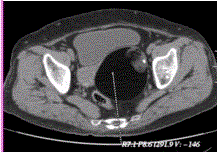

问题 患者女,36岁,CT发现盆腔内囊实性肿块,以囊性为主,含脂肪和钙化(下图),诊断应首先考虑为

选项 A.卵巢单纯囊肿 B.囊性畸胎瘤 C.卵巢囊腺瘤 D.卵巢囊腺癌 E.卵巢子宫内膜异位囊肿

答案 B